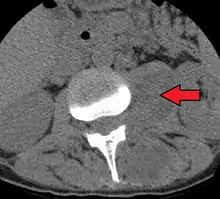

Paraspinal abscess in the psoas muscle